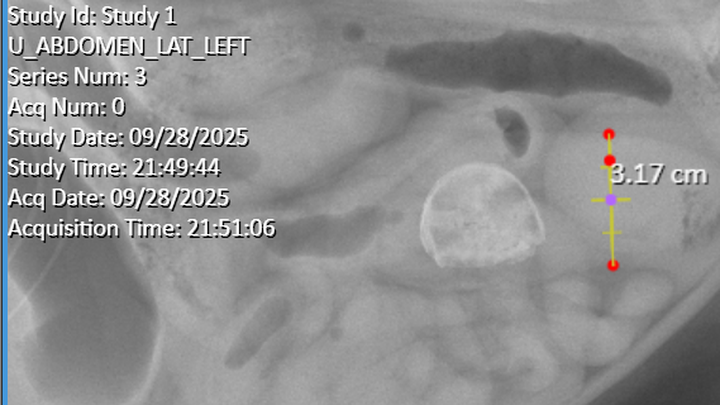

Hi! I'm Jude, I'm 24 years old. This is Parker, and as of this month he's 7 years old! I brought him home as a gift for my eighteenth birthday back in 2018, when he was just a couple months old. Parker is incredibly friendly and loving, a little guy that demands attention and cuddles at every opportunity. Recently, he's been getting sick. It's been pretty bad. We'd tried supervised feeding, changing his food, and nothing would work. He's been lethargic and showing clear signs of being in pain. Tonight (9/28/25) we took him to the vet because he refused his dinner-- something he's never done before. After a couple hours of tests and xrays, they found a foreign object in his stomach as well as some distension. Neither we nor the vets can tell what exactly it is, but we have been informed that he will more than likely need surgery to have it removed. We've been quoted somewhere between $3k-$5k. Please. I know it's cliche for people to say but he's my baby. I'm not ready to lose him. My partner and I are both college students and can't afford to do this on our own. I'm sorry. I know it's a lot and I am so sorry. But please, I can't lose my boy. Anything helps at all.